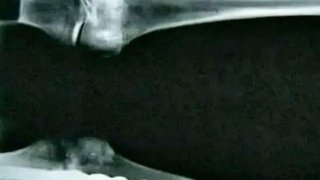

นี่คือสภาพของ..กะโหลกของผู้ป่วยมะเร็งกระดูก!😰

Bone Cancer กะโหลกของผู้ป่วยมะเร็งกระดูก นี่คือสภาพของกระดูกของคนที่ป่วยมะเร็งกระดูกในอดีตที่ถูกเก็บไว้เพื่อการศึกษาจนทำให้เกิดอาการที่คาดไม่ถึงแบบในภาพ ซึ่งมันถือเป็นโรคที่น่ากลัวอย่างมากเมื่อก่อนทำให้ผู้คนต้องล้มตายจากโรคนี้มากมายจนน่ากลัว จากในภาพจะเห็นว่าหัวกระโหลกที่มีรอยบวมปูดขึ้นมาจนน่ากลัว บางอันเป็นคล้ายกับขนที่ผุขึ้นตามกระดูกและชิ้นส่วนต่างๆของโครงกระดูกมนุษย์ ทำให้มันเป็นอีกโรคที่ถูกมอง.. ดูเพิ่ม

สภาพของกระดูกคนที่เป็นมะเร็งกระดูก

มะเร็งกระดูกสามารถทำให้กระดูกบวมและเปราะ เนื่องจากเซลล์มะเร็งทำลายโครงสร้างของกระดูก ก่อให้เกิดการเจริญเติบโตที่ผิดปกติและการกัดกร่อน นอกจากนี้ การเจริญเติบโตของกระดูกที่มากเกินไปอาจทำให้แคลเซียมในกระแสเลือดสูงเกินไป ซึ่งอาจนำไปสู่การหมดสติและเสียชีวิตได้ ดูเพิ่ม